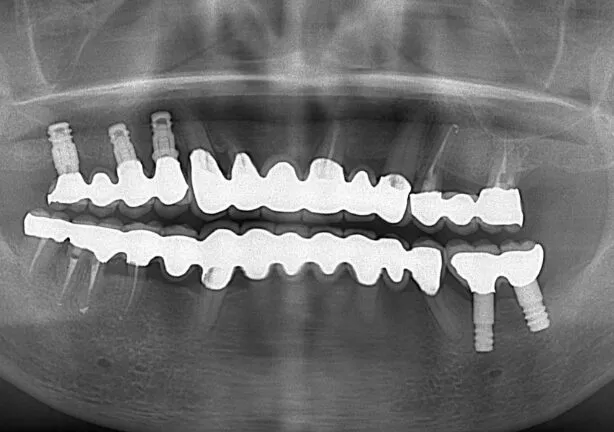

After

治療内容 | 口腔内診査〜カウンセリング

仮の義歯にて咬む位置の再設定 インプラント埋入 仮歯にてインプラントを含めた咬む位置の決定 最終的な被せ物(ジルコニア)の型取り〜装着 |

治療期間 | 4年(月2回の治療を要望されたため) |

治療回数 | 約100回 |

費用(税込) | 約¥8,800,000 |

リスク | 手術、並びに治療における疼痛 今後のメンテナンスが必須となる |